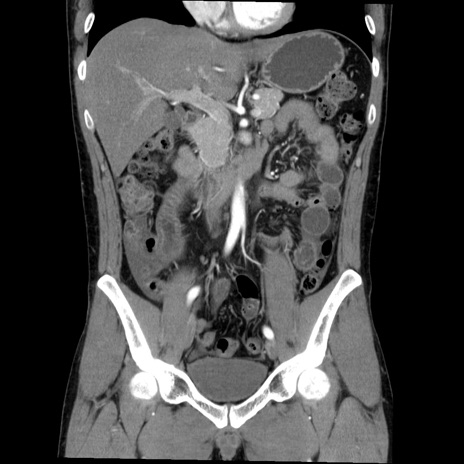

症例36(冠状断像)

【症例】20歳代 男性

【主訴】心窩部痛

【現病歴】今朝より上腹部痛あり。一旦軽快していたが再度出現したため救急要請。昨日夕に白身の魚を含む刺身を食べた。

【身体所見】BP 136/89mmHg、HR 74/min、BT 37.0℃、腹部:膨満、軟、心窩部に圧痛あり。反跳痛なし、筋性防御なし、腸雑音やや亢進あり。

【データ】WBC 17700、CRP 0.48